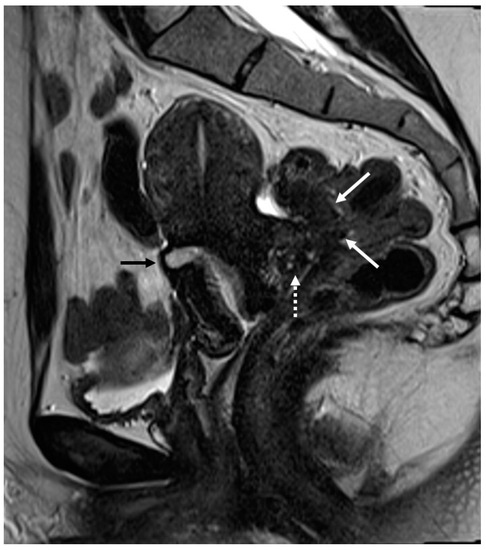

Figure 5.

External adenomyosis and intestinal endometriosis localization in 49-year-old female with story of multiple laparoscopy surgery. Sagittal T2WI shows a hypointense ill-defined subserosal mass in the posterior myometrium with hyperintense foci (long white arrow), suggestive for external adenomyosis, that cause retracting phenomena towards the anterior wall of the rectum. Additionally, there is deep endometriosis of the posterior compartment with hypointense nodule involving the serous and muscular layers of the anterior wall of the rectum (short white arrow).

Figure 6.

Retrocervical localization, intestinal mushroom cap sign and isthmocele in a 40-years old female. Retrocervical endometriosis localization (white dotted arrow), intestinal “mushroom cap sign” (white arrows) and isthmocele (black arrow).